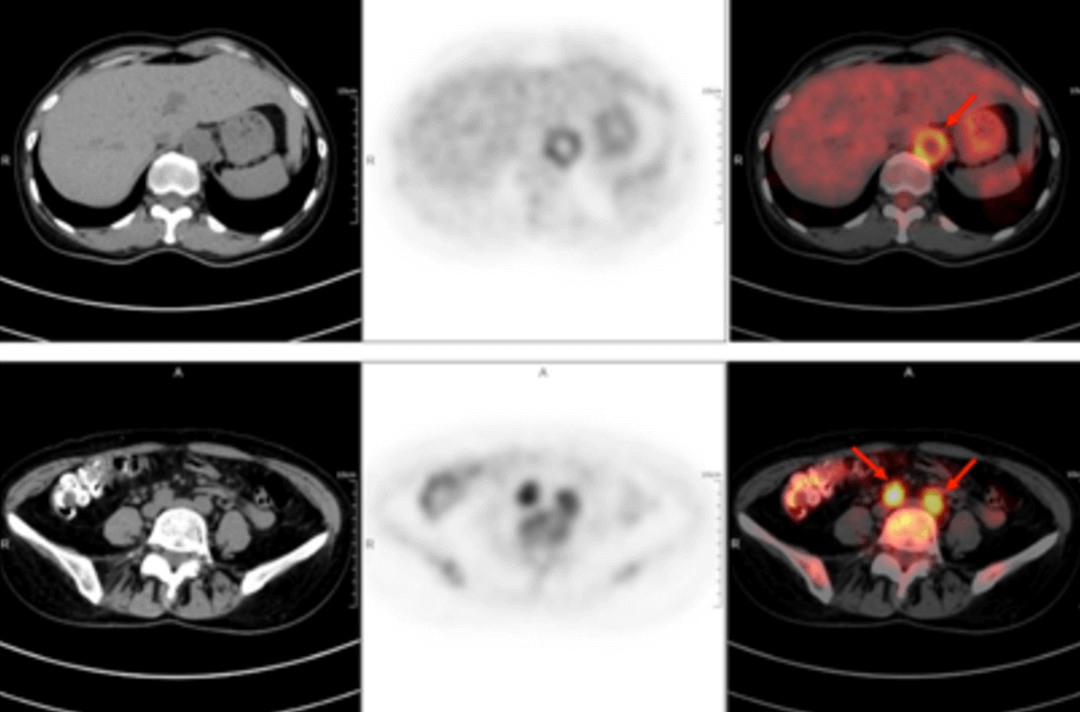

58歳の女性が40日以上前から断続的に発熱しているため受診しました。体温は38.9℃で、寒気、痰、喀血、胸痛、胸部圧迫感、息切れなどの症状はなく、倦怠感、肩関節痛が午後から夜間にかけて特に強く現れました。セファロスポリン系抗生物質の静脈内投与を2週間続けても改善は見られず、断続的な発熱が続いていました。外来診療では「原因不明の発熱」と指摘され、身体検査では明らかな診断上の特徴はありませんでした。血液検査の結果は以下の通りでした。赤血球沈降速度(最初の1時間):72mm、高感度C反応性蛋白:204. 20mg/lでした。その後、原因不明の発熱の原因を探るため、全身 F-FDG PET-CT 検査を行いました。

PET/CT 画像では,全身数カ所(両側内頚動脈,総頚動脈,腕頭動脈,両側鎖骨下動脈,腋窩動脈,胸部大動脈,腹部大動脈,両側総腸骨動脈,内腸骨動脈,外腸骨動脈,大腿動脈)に糖代謝亢進を伴う壁厚化を認め,炎症性変化によるものと判断しました。病歴、臨床症状、検査、画像所見を総合してT.A.と診断し、標準的な抗炎症治療を行ったところ、体温が低下し病状が改善しました。